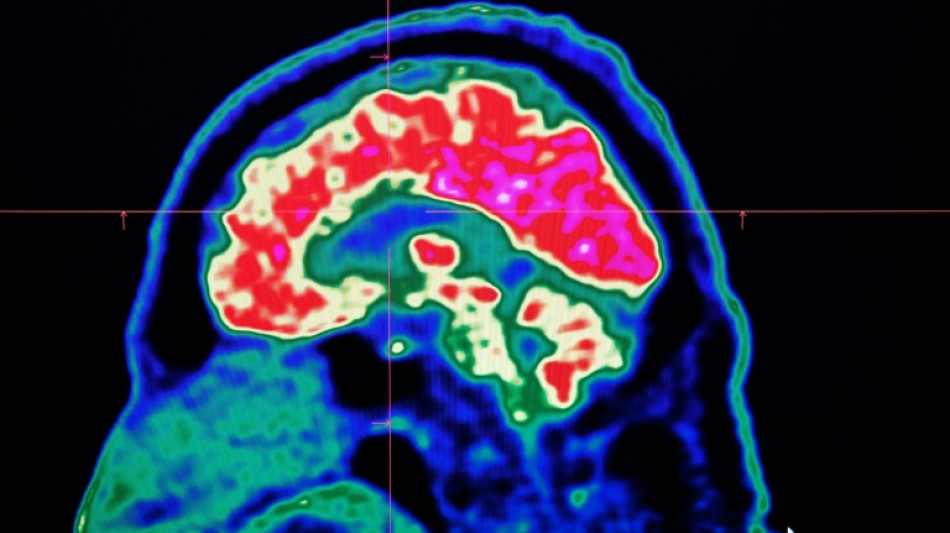

Final report casts doubt on existence of Canada mystery brain illness / Photo: Fred TANNEAU - AFP

A Canadian medical report published Friday found no evidence linking environmental factors to an unusual set of neurological symptoms affecting hundreds of people, a five-year saga that has shaken a small Atlantic province.

In 2021, health officials in New Brunswick launched an investigation involving 48 patients with a range of neurological symptoms but no apparent common illness. These included muscle spasms, memory loss, hallucinations and balance issues.

Some in the province of less than a million people began describing the condition as a mystery brain disease.

Provincial officials said at the time that the patient group could be suffering from a new disease not previously seen in Canada and began using the term "possible neurological syndrome of unknown cause."

But the provincial investigations that followed, including the final report released Friday, dismissed claims that there was anything linking the patients other than a reported set of symptoms -- and a single neurologist, named Alier Marrero.